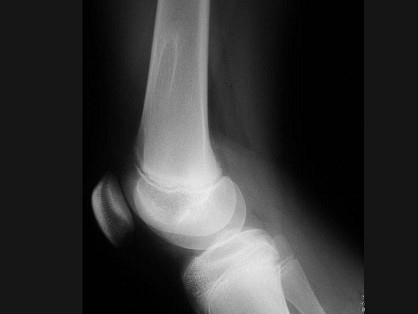

问题 男,13岁,运动后膝痛,请结合影像图像,选择最可能的诊断 ( )

选项 A、成骨细胞瘤 B、骨样骨瘤 C、动脉瘤样骨囊肿 D、骨软骨瘤 E、正常影像

答案 D